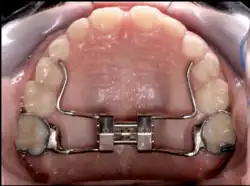

Upper and lower jaw functional expanders

A typical treatment for incorrectly positioned teeth (malocclusion) takes from one to two years, with braces being adjusted every four to 10 weeks by orthodontists,[31] while university-trained dental specialists are versed in the prevention, diagnosis, and treatment of dental and facial irregularities. Orthodontists offer a wide range of treatment options to straighten crooked teeth, fix irregular bites, and align the jaws correctly.[32] There are many ways to adjust malocclusion. In growing patients, there are more options to treat skeletal discrepancies, either by promoting or restricting growth using functional appliances, orthodontic headgear, or a reverse pull facemask. Most orthodontic work begins in the early permanent dentition stage before skeletal growth is completed. If skeletal growth has completed, jaw surgery is an option. Sometimes teeth are extracted to aid the orthodontic treatment (teeth are extracted in about half of all the cases, most commonly the premolars).[33]

Palatal expansion

Palatal expansion can be best achieved using a fixed tissue-borne appliance. Removable appliances can push teeth outward but are less effective at maxillary sutural expansion. The effects of a removable expander may look the same as they push teeth outward, but they should not be confused with actually expanding the palate. Proper palate expansion can create more space for teeth as well as improve both oral and nasal airflow.[41]